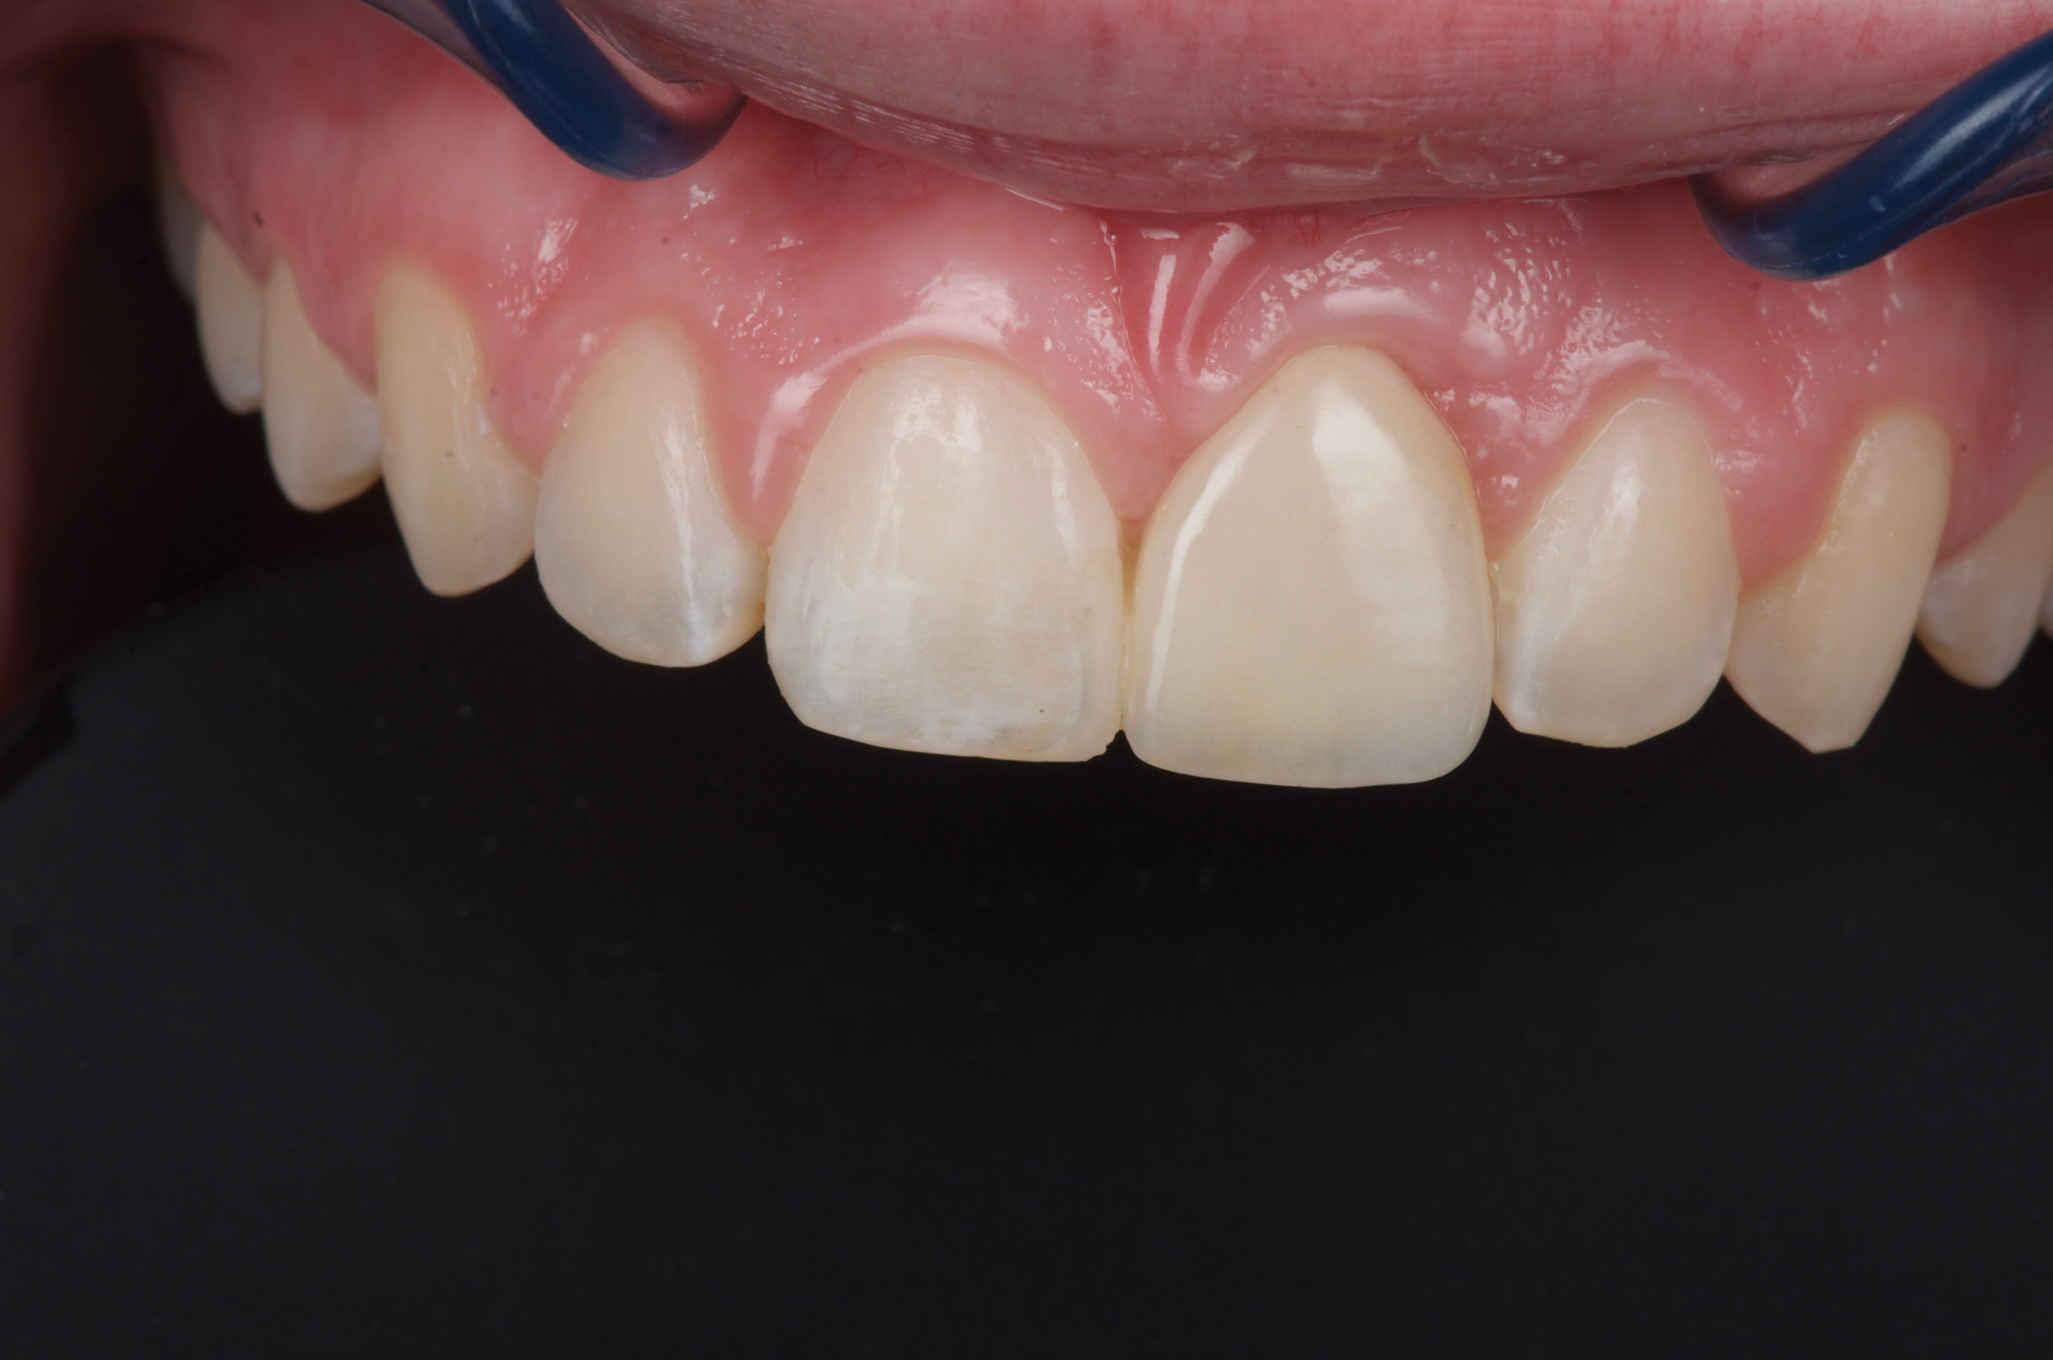

Canine substitution can be an excellent alternative for the replacement of the missing maxillary lateral incisor (Figure 1 and Figure 2). This treatment option can be particularly effective if the canine has a flat facial surface, is not too wide mesiodistally, and has a color similar to the contralateral lateral incisor. Patients with missing lateral incisors who present with maxillary dentoalveolar protrusion and/or an Angle class II molar relationship and minimal crowding in the mandibular arch are considered excellent candidates for canine substitution.7

Fig 1. Patient was missing teeth Nos. 7 and 10 (Fig 1). Canine substitution was the treatment used to replace these missing teeth (Fig 2).

Figure 1

Fig 2. Patient was missing teeth Nos. 7 and 10 (Fig 1). Canine substitution was the treatment used to replace these missing teeth (Fig 2).

Figure 2